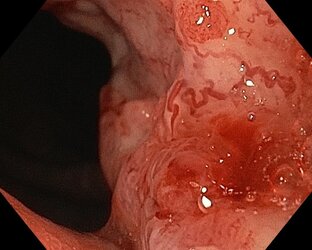

00:271,0×00:00/00:27ПодборкаДневник эндоскописта2001 смотрели · 3 года назадПодписатьсяЭрозии желудка